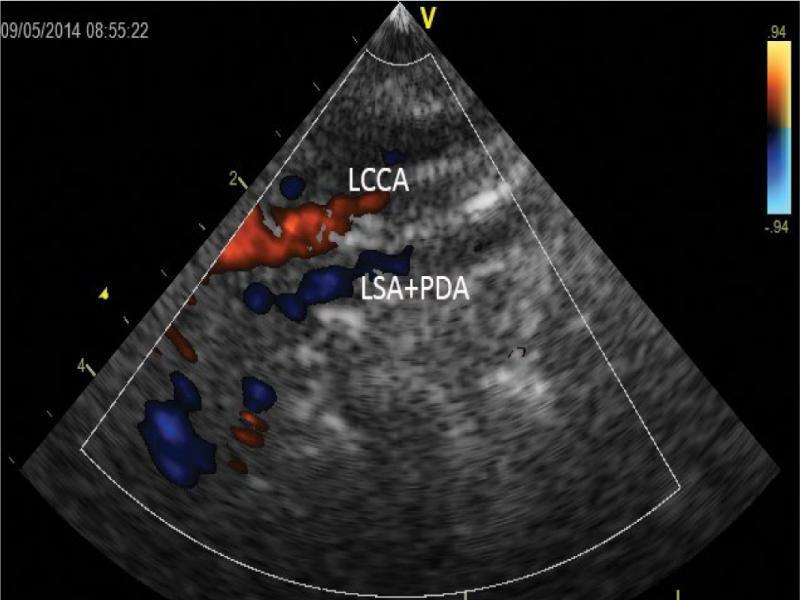

Systole. Further shift of the ultrasound beam to the left side – two close parallel vessels with opposite directions of flow: the left common carotid artery (LCCA) coded in red and the left subclavian artery with ductus arteriosus coded in blue (LSA + PDA)

Subsequent images were recorded by gradually moving the ultrasound beam bottom-to-top. Figure 6, Fig. 7 and Fig. 8 show a series of upper mediastinal vessel sections in a plane similar to sagittal plane. Subsequent images were acquired by moving the ultrasound beam from the median plane toward the left side of the patient). The pulmonary trunk originated from a hypoplastic, relatively short outflow tract. The diameter of the ostium of the outflow tract was about 4 mm (stenosis due to hypertrophied septomural trabeculae and displacement of the infundibular septum) in the midportion – about 8 mm. A tortuous patent ductus arteriosus with increased flow was detected, most probably originating from the left subclavian artery or left brachiocephalic trunk. The examination was hampered by very poor echogenicity of this region due to the absence of thymus.